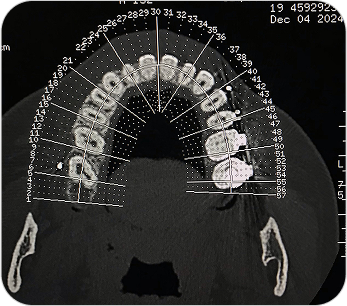

Dental Scan (Tomografía 3D Dental)

El Dental Scan o Tomografía Computada de Haz Cónico (CBCT) es un estudio especializado que brinda imágenes tridimensionales de alta resolución del sistema dentomaxilofacial. Es fundamental en odontología avanzada, permitiendo planificaciones precisas y diagnósticos más seguros.

La tomografía dental (CBCT) es un estudio esencial en odontología avanzada, que permite ver el maxilar, mandíbula y piezas dentales en 3D para diagnósticos y tratamientos más seguros.

¿PARA QUÉ SE UTILIZA?

- Planificación de implantes dentales con medición exacta del hueso.

- Evaluación de muelas del juicio o dientes incluidos.

- Estudio de quistes, tumores o lesiones óseas de mandíbula y maxilar.

- Diagnóstico de patología articular (ATM).

- Detección de fracturas, reabsorciones o infecciones profundas.

- Cirugías ortognáticas y procedimientos maxilofaciales complejos.

¿POR QUÉ ES UN ESTUDIO DESTACADO?

- Imágenes en 3D reales y de alta definición.

- Mucho más preciso que una radiografía panorámica tradicional.

- Estudio rápido, cómodo y con baja dosis de radiación.

Dental Scan (Tomografía 3D Dental)

El Dental Scan o Tomografía Computada de Haz Cónico (CBCT) es un estudio especializado que brinda imágenes tridimensionales de alta resolución del sistema dentomaxilofacial. Es fundamental en odontología avanzada, permitiendo planificaciones precisas y diagnósticos más seguros.

La tomografía dental (CBCT) es un estudio esencial en odontología avanzada, que permite ver el maxilar, mandíbula y piezas dentales en 3D para diagnósticos y tratamientos más seguros.

¿PARA QUÉ SE UTILIZA?

- Planificación de implantes dentales con medición exacta del hueso.

- Evaluación de muelas del juicio o dientes incluidos.

- Estudio de quistes, tumores o lesiones óseas de mandíbula y maxilar.

- Diagnóstico de patología articular (ATM).

- Detección de fracturas, reabsorciones o infecciones profundas.

- Cirugías ortognáticas y procedimientos maxilofaciales complejos.

¿POR QUÉ ES UN ESTUDIO DESTACADO?

- Imágenes en 3D reales y de alta definición.

- Mucho más preciso que una radiografía panorámica tradicional.

- Estudio rápido, cómodo y con baja dosis de radiación.